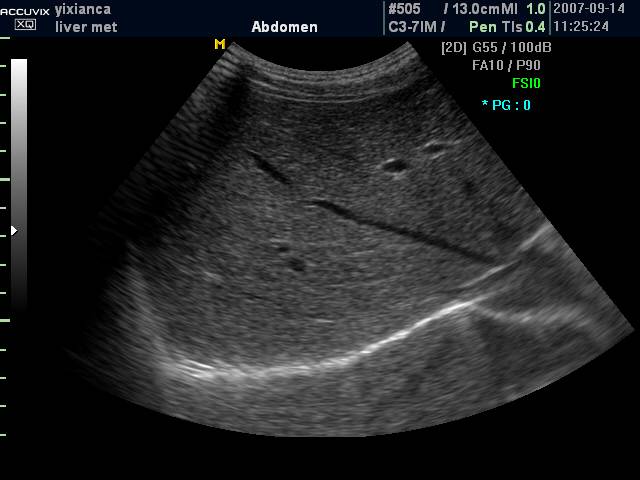

(二)通过肝静脉进行分叶

肝静脉主干在叶间裂或段间裂内行走,易于超声显示,最便于进行肝脏分叶、分段。

1. 肝右静脉行走于右叶间裂内-右前、后叶分界

2. 肝中静脉行走于正中裂的后半部和尾状叶内,右半肝与左半肝分界

3. 肝左静脉近端走行左叶间裂内-左内外叶分界

4. 肝左静脉远端位于左段间裂内-为左外叶上段和下段分界

肝左右叶的超声分界标志(肝中静脉)

肝左右叶的超声分界标志(胆囊切迹-下腔静脉左缘连线)